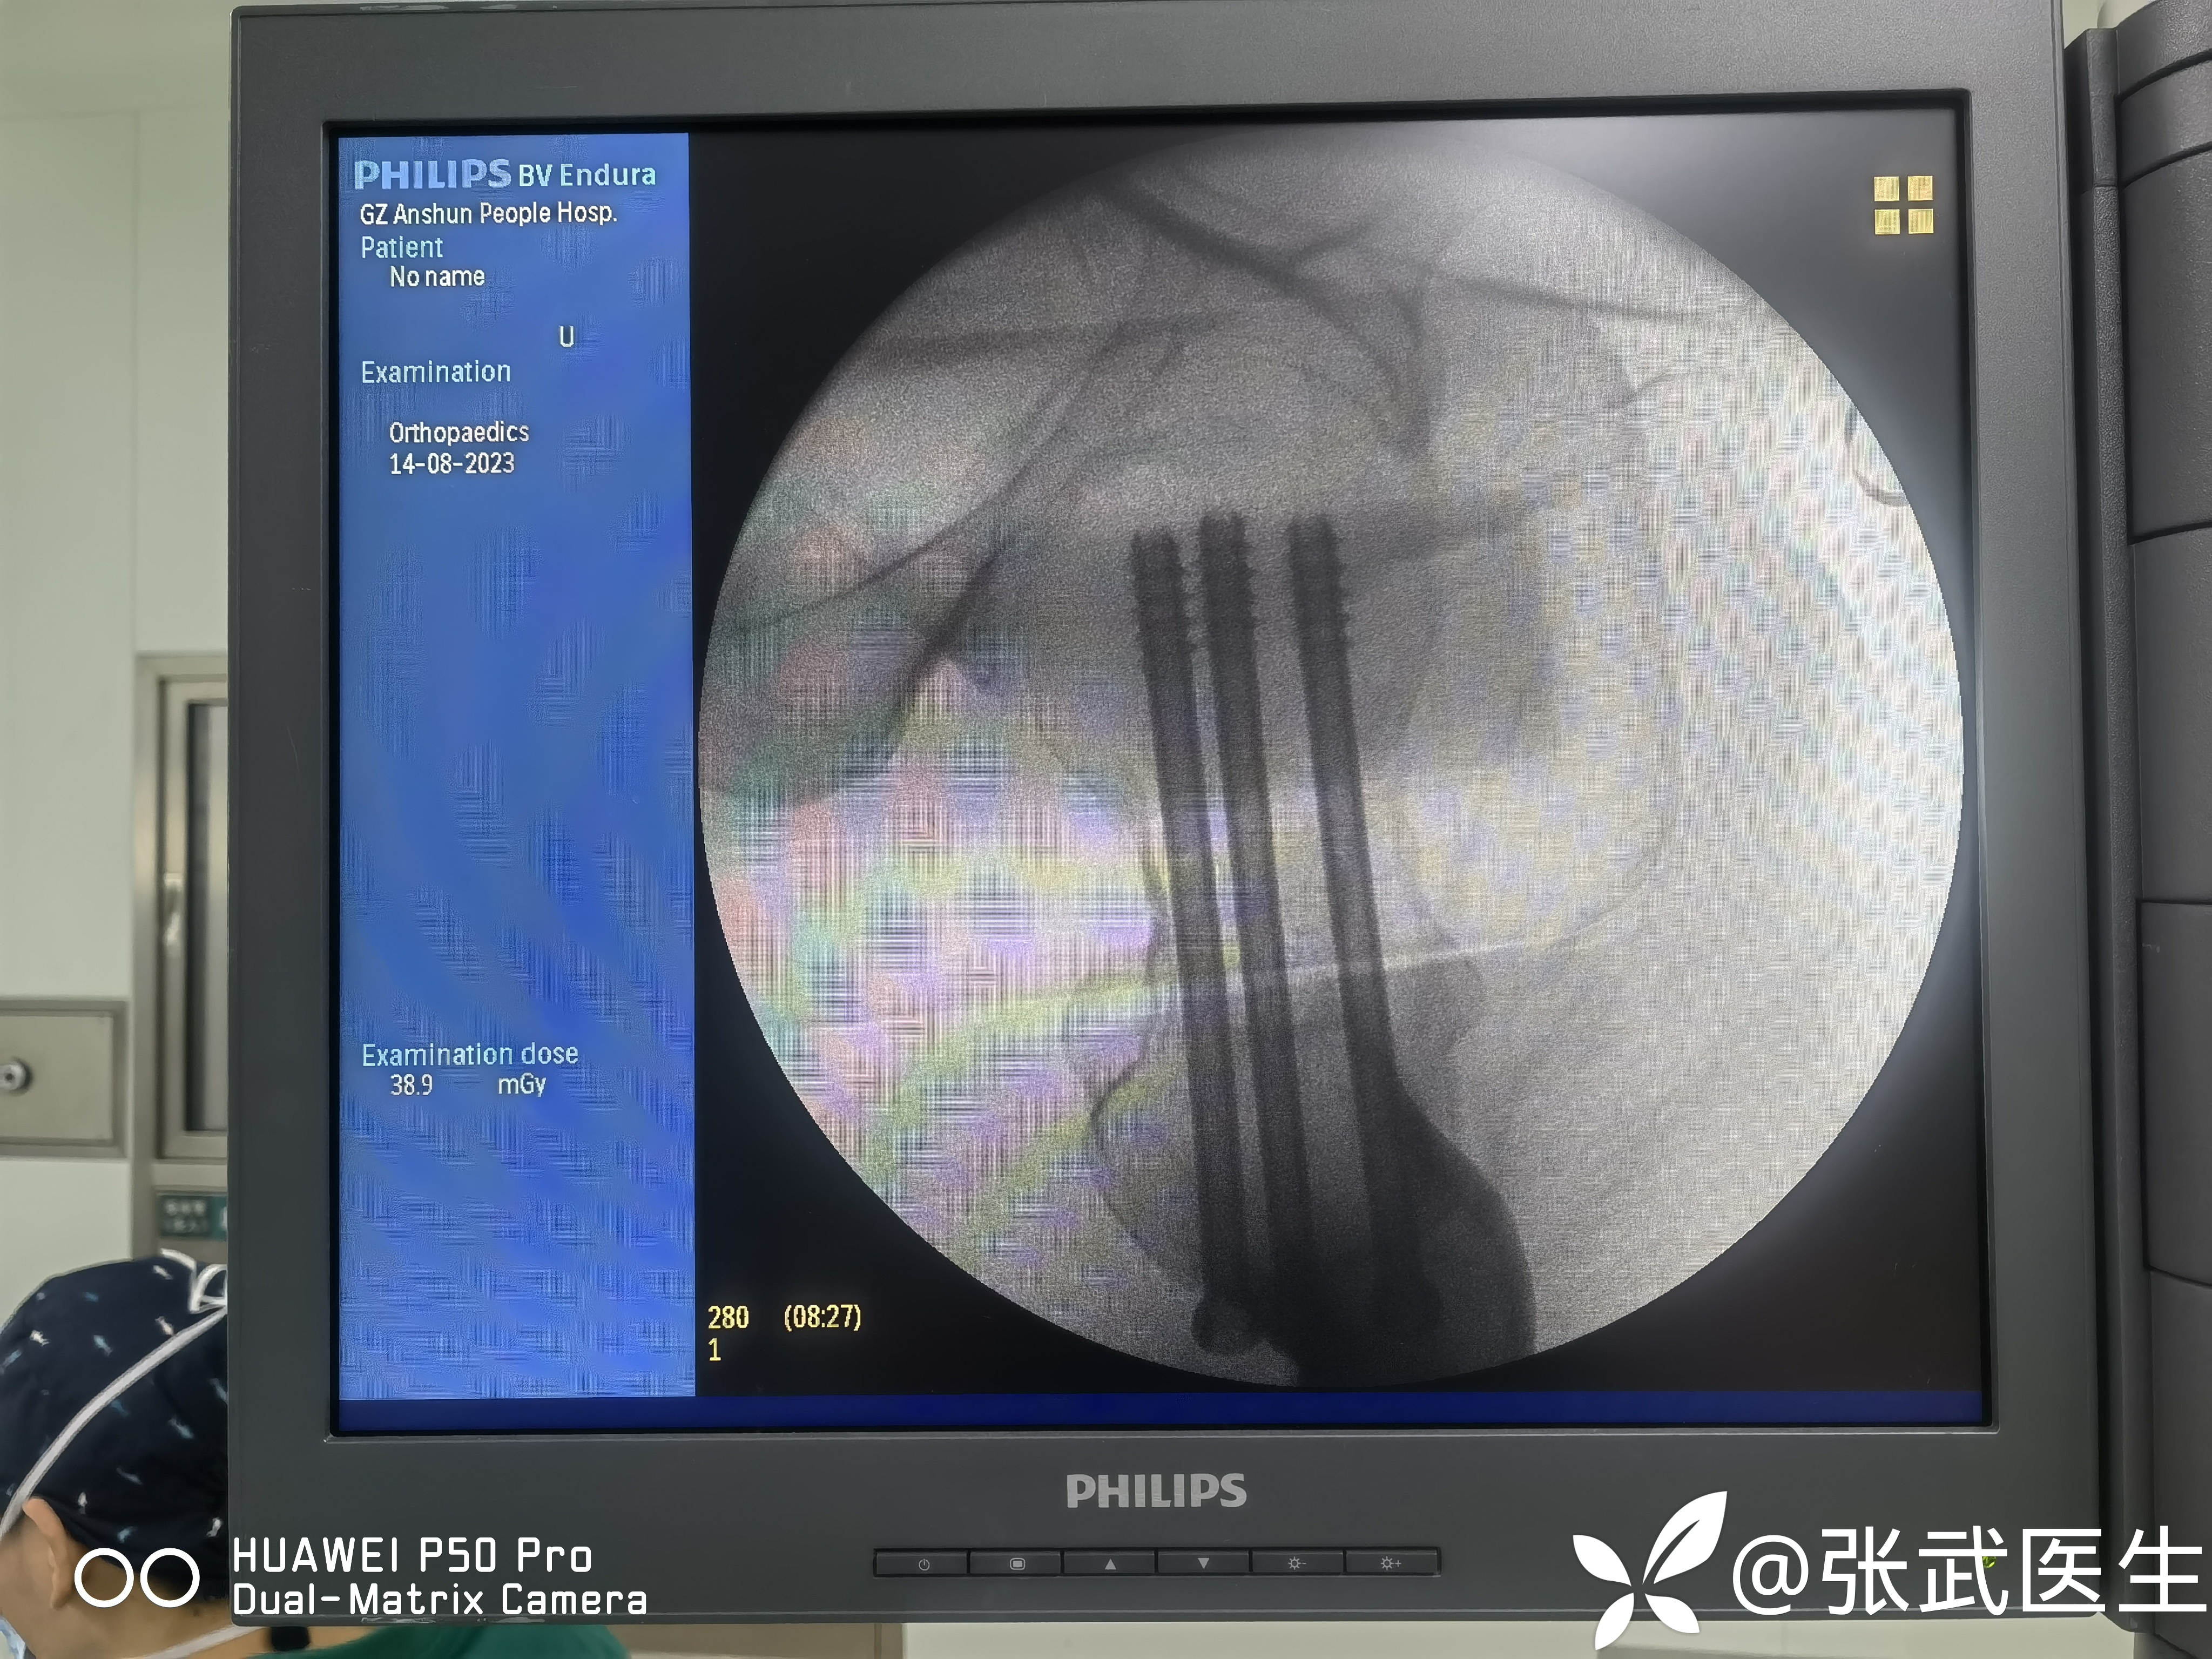

克氏针置入情况

先置入股骨距克氏针,以此为参照物置入另两枚,呈倒三角。

分别置入7.3mm*95mm 7.3mm*90mm 7.3mm*90mm三枚

骨折复位

置钉呈平行,分散,靠边。